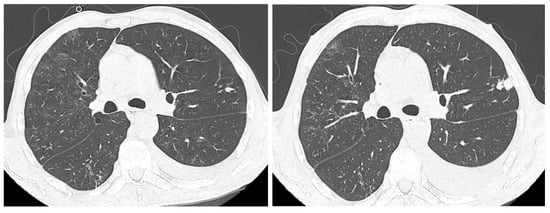

The CT scan performed at the initiation of treatment revealed micronodular “tree-in-bud” infiltration predominantly in the upper half (Figure 2), bilaterally, with left-sided pleural effusion and large-volume fluid in the abdominopelvic cavity.

Figure 2. “Tree-in-bud” infiltration in the posterior segment of the right upper lobe (RUL) before treatment.